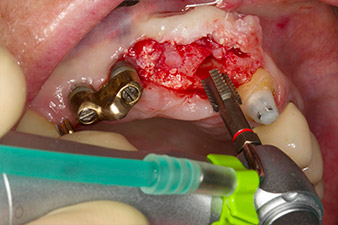

Der Alveolarknochen erweist sich an Position 22 als ausreichend dimensioniert. Die Abbildungen 2 und 4 zeigen die Implantatbett-Aufbereitung, den Gewindeschnitt und die Implantation mit dem Implantmed.

Der neue Implantologiemotor wird jeweils mit den geeigneten chirurgischen Winkelstücken von W&H verwendet.